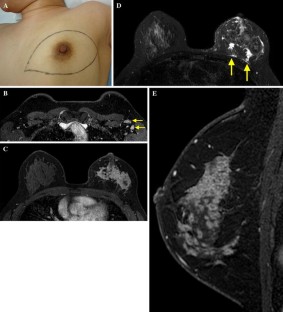

Fig. 3